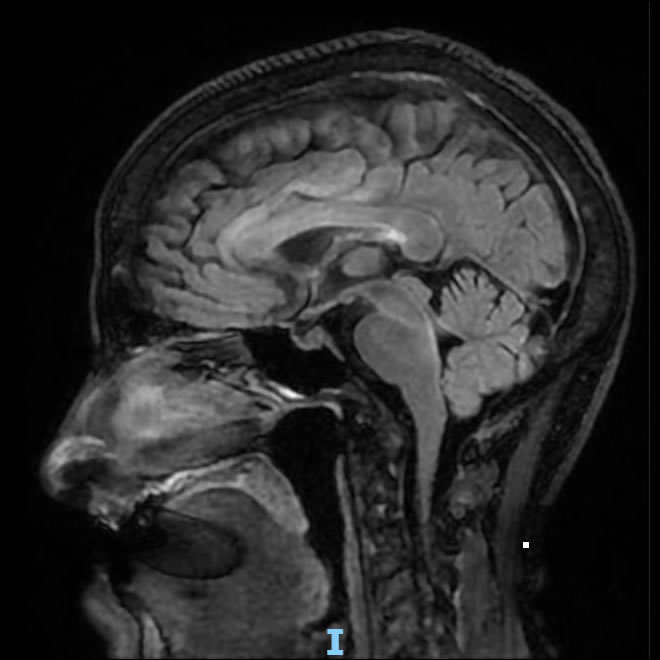

Mayo 2025. Sanatorio Allende Paciente femenina de 71 años de edad con antecedente de cáncer de mama en tratamiento, consulta por fiebre y comienza con deterioro del sensorio.